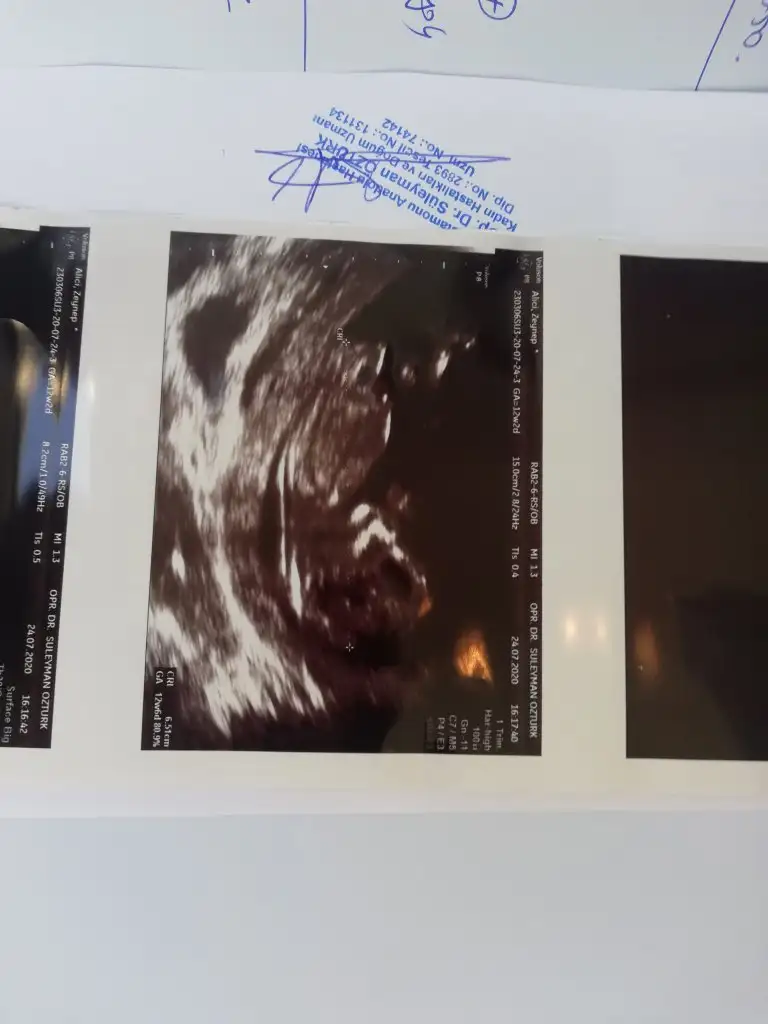

Erkek gibi yinede 12-13 hafta usgde paylasinMerhaba ikra meyra benim bebişim içinde tahminde bulunurmusun rica etsem

Buna göre erkek ama en iyi 11 12 13 haftalar daha minik minnoş cnm

Çok teşekkür ederim ilerleyen zamanlarda yine atarımBuna göre erkek ama en iyi 11 12 13 haftalar daha minik minnoş cnm